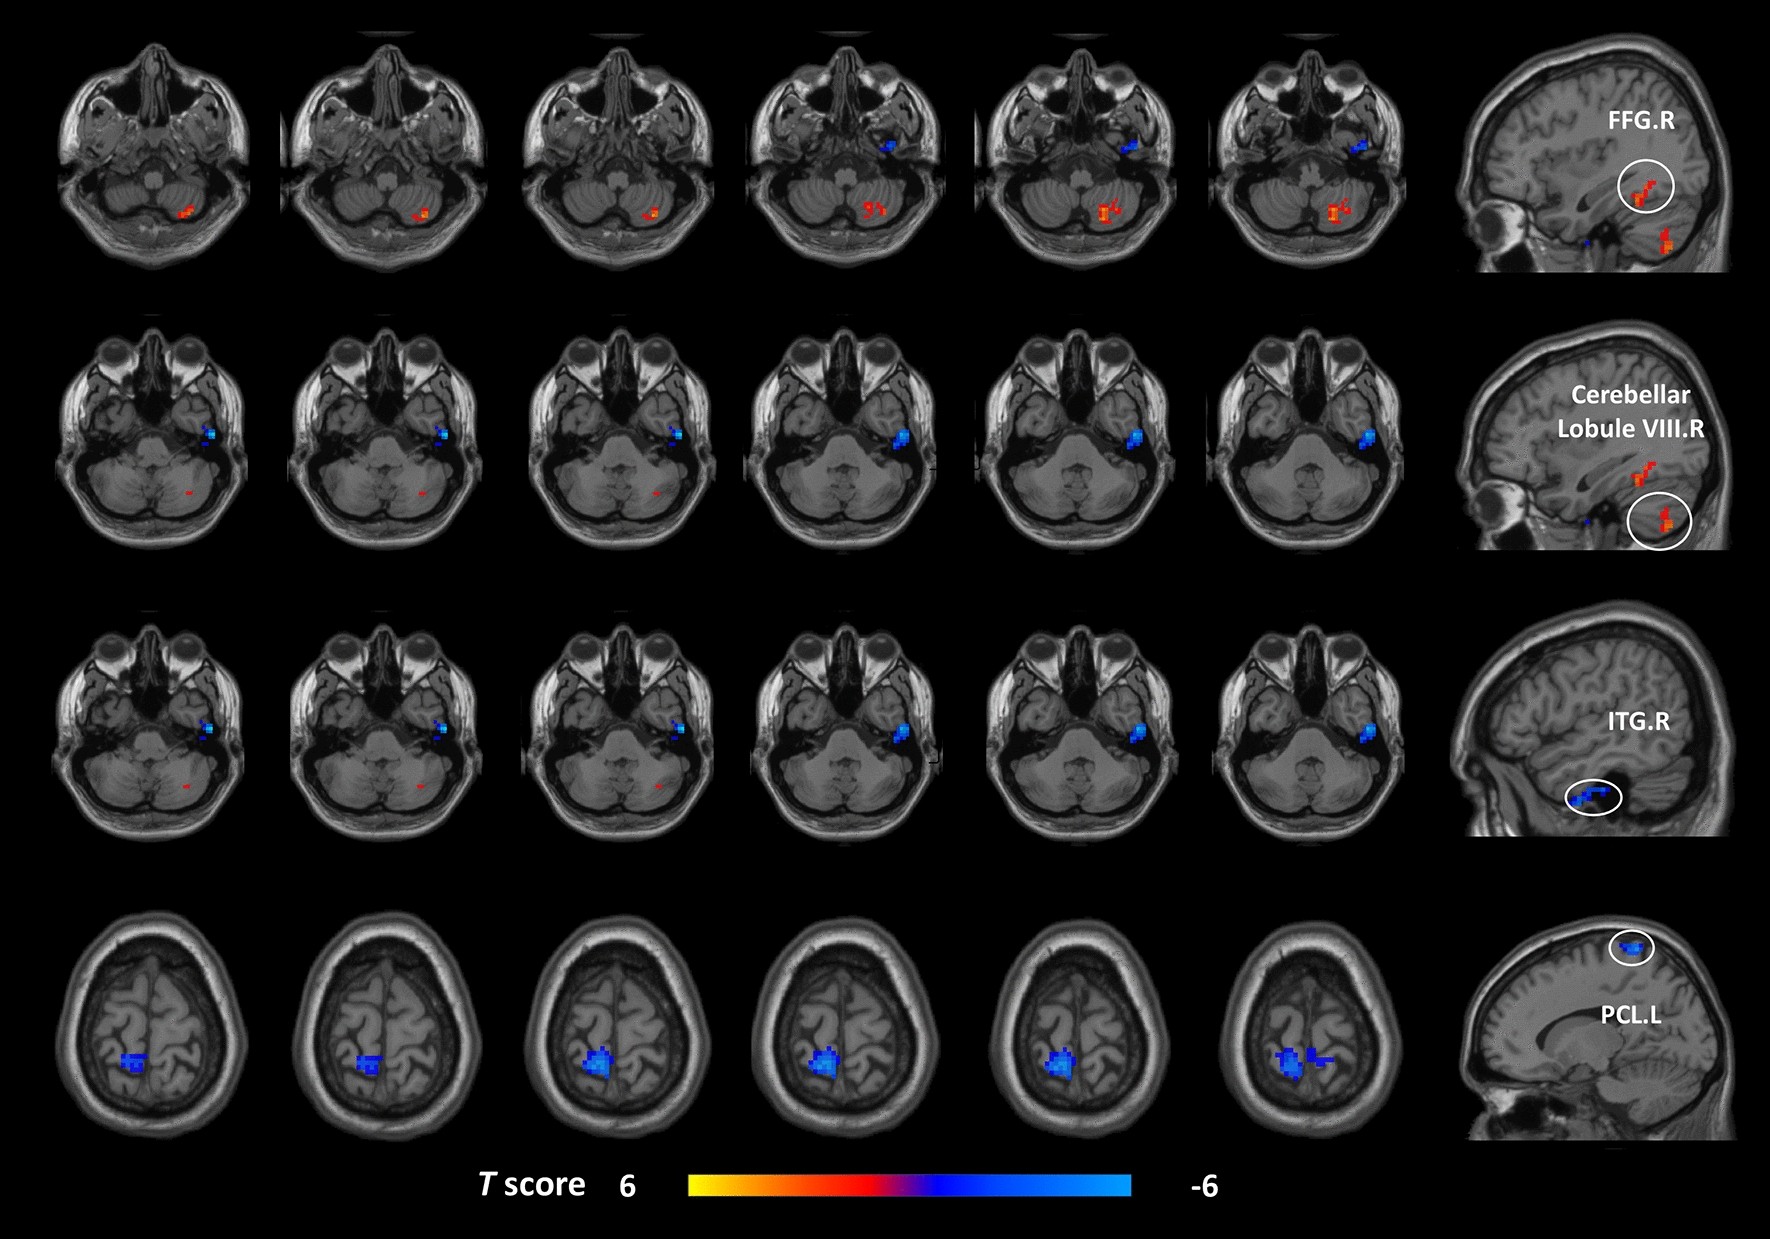

Figure 1

Brain regions exhibiting differences in voxel-wise DC between the MwoA patients and the HCs (GRF corrected, voxel p < 0.005, cluster p < 0.05). The color bar represents the t-score. Warm color represents regions with higher DC values in the patients compared to HCs; Cool color represents areas with lower DC values in the patients compared to HCs. DC degree centrality, MwoA migraine without aura, HCs healthy controls, GRF Gaussian random field, FFG fusiform gyrus, ITG inferior temporal gyrus, PCL paracentral lobule, R right, L left.